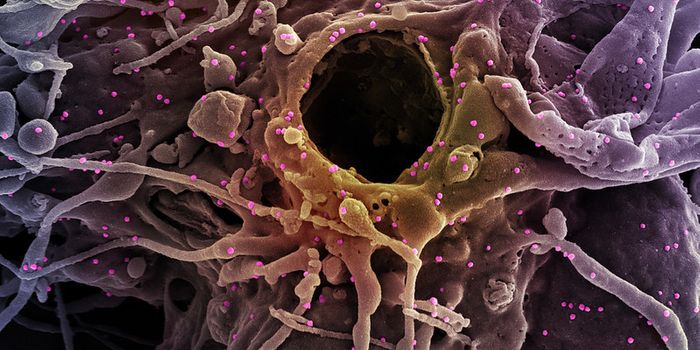

FEB 13, 2025ImmunologyImmunotherapy has changed the way physicians treat cancer patients. This approach to therapy targets the immune system t ...

FEB 09, 2025CancerGlioblastoma (GBM), an aggressive form of cancer that grows in the brain or spinal cord, occurs at an incidence rate of ...

DEC 09, 2024CancerCancer cells have evolved sophisticated strategies to evade the immune system, prolonging their survival and growth.&nbs ...